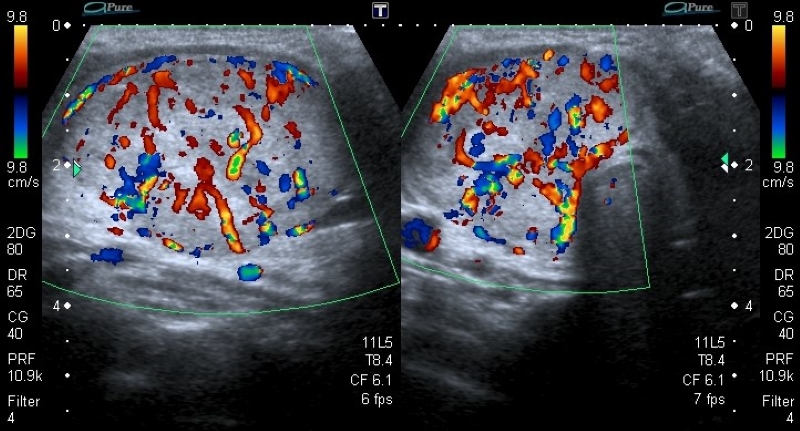

Vascularización

La vascularización se evalúa con la herramienta de Doppler color, y se debe determinar si esta se encuentra ausente (Fig. 18) o aumentada en el nódulo en relación con el parénquima tiroideo. La vascularización aumentada puede presentar dos patrones: central (Fig. 19) y periférico (Fig. 20), siendo el aumento de la vascularización central con disposición caótica la que presenta mayor riesgo de malignidad2,14,19,22,23,24. Un patrón vascular periférico se asocia mayormente con benignidad15,18, aunque algunos autores han calificado a la vascularización como una característica no significativa para diferenciar nódulos benignos de malignos2,3,14,16.